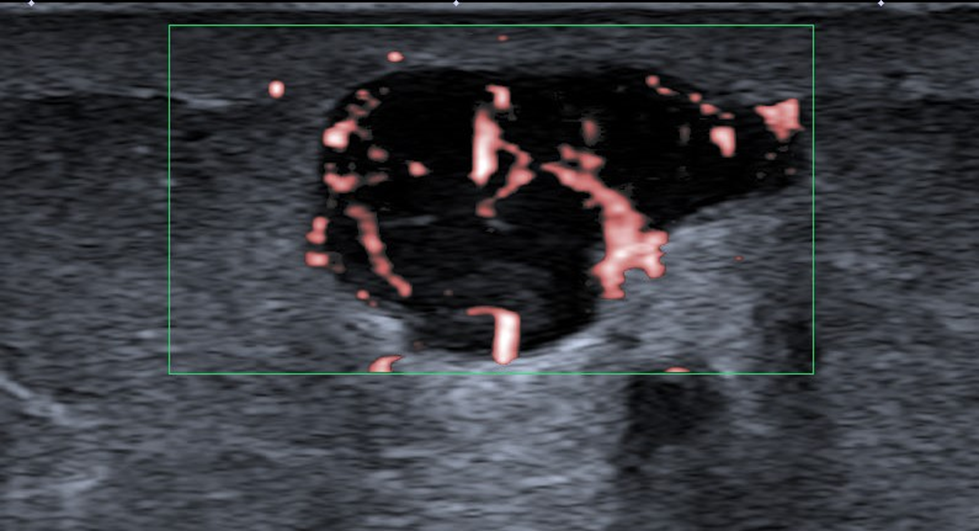

Métastase sous-cutanée de mélanome, vascularisée, dépistée en échographie

L’échographie ganglionnaire est l’examen le plus performant, permettant l’analyse morphologique (forme, hile, cortex) et le guidage de micro-biopsies. Si l’échographie est normale, la technique du ganglion sentinelle est parfois proposée.